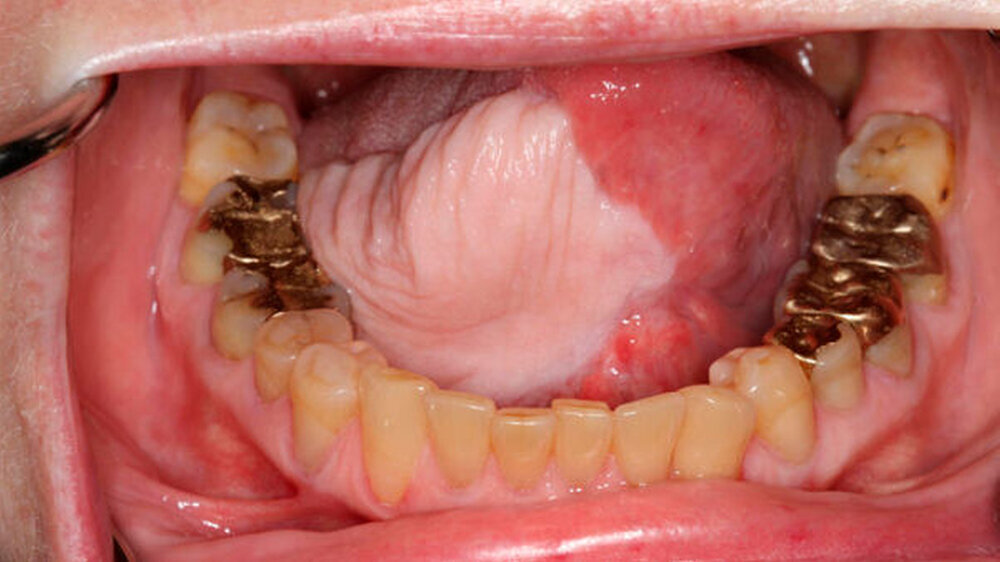

Sie berichtete, dass sie seit etwa sechs Monaten eine auffällige Veränderung der Mundschleimhaut an der vorderen Zungenunterseite sowie am rechten Zungenrand bemerkt habe. Bis vor 34 Jahren habe sie insgesamt zehn Jahre regelmäßig geraucht. Neben einer Schilddrüsenunterfunktion waren keine weiteren Erkrankungen bekannt.

Zunächst wurden Proben zur mikroskopischen Begutachtung entnommen, woraufhin sich die Diagnose einer bösartigen Krebsformation der Mundschleimhaut bestätigte. In den sich anschließenden Untersuchungen zeigten sich keine weiteren auffälligen Befunde oder Absiedlungen des Tumors in der Mundhöhle.